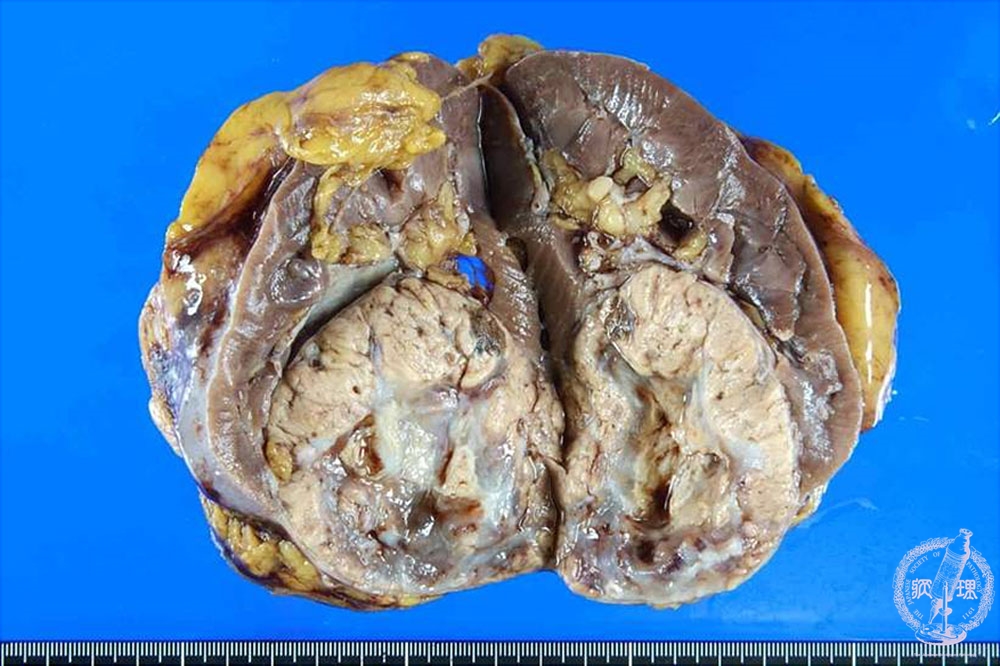

- ★(17)Renal cell carcinoma

Gross findings: Renal cell carcinoma presents a well-demarcated mass (yellow dotted line). In most cases, the tumor presents yellowish color.